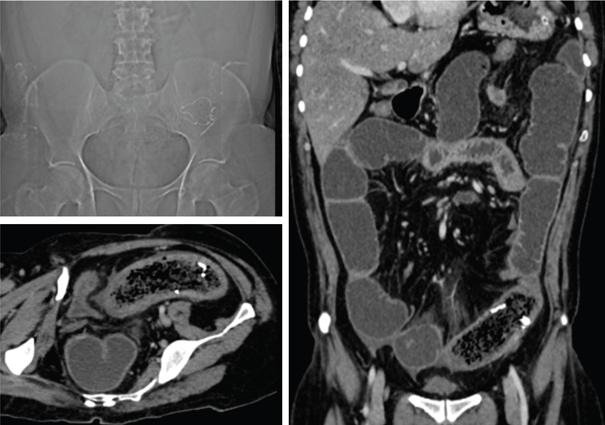

SMALL BOWEL IMAGING Poonam Narang, Himanshu Gupta The small bowel is a long tubular hollow abdominal viscus thrown into intricate folds and loops and packed into the abdominal cavity. It is approximately 5–7 m in length and extends from the gastric pylorus up to the ileo-caecal valve. It is anatomically divided into three parts: duodenum (meaning ‘in twelves’ as its length is roughly equal to the width of 12 fingers), jejunum (meaning ‘fasting’ as it was usually found empty after death) and ileum. The duodenum measures 20–25 cm in length and extends from gastric pylorus to the ligament of Trietz. It is a fixed ‘C’-shaped structure that cradles pancreatic head in its concavity. First part of the duodenum is a triangular conical structure with its base communicating with gastric antrum. Its apex points to the right and cranially, in close apposition with the gall bladder and the under surface of the liver. Second part of duodenum is almost vertical, lying in the right paravertebral gutter. The common bile duct courses obliquely posterior to it and drains at a papilla at its medial wall (the Ampula of Vater), after joining with the main pancreatic duct. Third part is horizontal, crossing the midline between the superior mesenteric artery (SMA) and aorta from right to left, caudal to pancreatic neck. Fourth part is again almost vertical, ascending left of the spine almost to the level of duodenal bulb and transitions to jejunum at duodenojejunal (DJ) flexure. Duodenum is mostly a retroperitoneal structure while the rest of the small bowel acquires a mesentery at the DJ flexure. The jejunum and ileum are intraperitoneal structures, suspended in the abdominal cavity from the posterior abdominal wall by the free end of their ‘fan-shaped’ mesentery and are thus relatively mobile. Though considered a part of small bowel, duodenum differs from the rest of the small bowel in structure as well as function. Plethora of the diseases that affect duodenum are distinct. Peptic ulcer disease affecting the first part does not affect the rest of the small bowel. Most other diseases affecting the duodenum arise from the surrounding structures like pancreas, gall bladder, bile duct, liver and the hepatic flexure of colon. Hence, on imaging, duodenal abnormalities should prompt a search for pathologies of the surrounding organs. While duodenum is structurally a distinct segment, the structural transition from jejunum to ileum is seamless, with no external demarcating point. Histologically, and also on imaging, all three segments have clear identities. Their mucosal lining, folds and presence of submucosal lymphoid follicles are allocated in accordance with their specific functions. Jejunal loops occupy left hemiabdomen and ileal loops, with ileo-caecal junction, lie in the right lower abdomen. Jejunum is about two-fifths of the length of the small bowel, and the ilium forms the rest of the three-fifths of the entire 5–7 m. ‘Terminal ileum’ is a term arbitrarily but commonly used in clinical practice to denote the portion of ileum just proximal to ileo-caecal junction harbouring abundant lymphoid tissue in its walls and playing host to a number of pathologies. At ileo-caecal junction, the ileum joins the caecum obliquely. A valve-like mucosal fold regulates the flow of digested food into the colon and prevents its reflux back. Its efficiency in preventing reflux is quite inconsistent in a large percentage of subjects. The arterial supply of the duodenum is by the branches of hepatic artery (branch of Celiac Axis artery), till the proximal half of second segment (marked by the Ampula of Vater); and by branches of the superior mesenteric artery beyond that point. Duodenal branches of respective superior and inferior pancreatico-duodenal arteries make an arcade along the medial margin of duodenum in the pancreatico-duodenal groove. The rest of the small bowel is supplied by the superior mesenteric artery and its branches while venous drainage is via superior mesenteric vein and its tributaries. These vessels traverse the mesentery, between the twofolds of the peritoneum from the posterior abdominal wall to reach the small bowel forming multiple arcades of vessels within the mesentery. Straight arteries, called the Vasa Recta, arise from the terminal arcade and enter the bowel wall, along its mesenteric border. Disease processes involving the specific artery affects the respective bowel segment that it supplies. Ischaemia, infarction and haemorrhage can be attributed to and localized correctly based on the relevant vascular anatomy. Inflammatory diseases cause engorgement of Vasa recta; and at times, identifying them as a lead point, one is able to localize the involved bowel segment correctly. Vascular ischaemia affects the antimesenteric part of the bowel earlier in the course of the disease. Therapeutic procedures too can be appropriately planned based on the vascular territory of the affected bowel segment. The mesentery forms a fan-shaped suspensory support, tethering the small bowel to the posterior abdominal wall, along a line running obliquely from ligament of Trietz (in LUQ) to ileo-caecal junction close to superior part of right sacro-iliac joint (in RLQ). This ‘root of mesentery’ averages about 15–20 cm in length. It is closely wrapped around small bowel loops and merges with the serosa. All lymphatic and vascular channels supplying to and draining from the small bowel traverse within the mesentery. Thus, pathology originating in one often affects the other by contiguity, haemodynamic alteration or haemo-lymphatic spread. The normal mesentery sandwiches a layer of fat between its two leaves. On imaging, it provides a good background against which identification of pathologies of fluid density (oedema) or soft tissue density (phlegmon, lymph nodes, masses) can be made. Mesenteric oedema often becomes the smoke leading up to the fire, for example: focal oedema adjacent to the site of an otherwise invisible bowel wall perforation. On ultrasound, such tell-tale inflammation is seen as an increase in the echogenicity of mesenteric fat adjacent to the site of bowel pathology. On CT, the hypodense fat becomes hyperdense whenever any pathological change occurs. Delineation of mesenteric vessels is also facilitated due to surrounding hypodense fat. Engorged Vasa recta are easy to identify on imaging as they stand out against the surrounding fat in the mesentery. Similar imaging findings can be extrapolated to MR as well. Similar to the rest of the gastrointestinal tract, the small bowel wall comprises four layers (strata) – from within outwards being mucosa, submucosa, muscularis propria and serosa. Mucosal folds (Valvulae Conniventes) and further finger-like projections of mucosa (Villi) help dramatically increase the surface area for absorption. Only valvulae conniventes are seen radiologically as concentric rings measuring 2–3 mm. The bowel wall measures 1–2 mm when distended and 2–3 mm when collapsed symmetrically in its entire circumference. Increased bowel wall thickness (in the background of adequate luminal distension) is a commonly used marker of pathology. Understanding how different pathologies target specific sites within the micro-structure of bowel wall, along with length of bowel involvement, could be helpful in drawing conclusion regarding the etiopathogenesis. For example, short segmental disruption of the entire thickness of bowel wall favours a unifocal, infiltrative pathology-like malignancy. Long segment submucosal oedema with preserved mucosal integrity/enhancement may be a haemodynamic phenomenon as in portal enteropathy or reactive as in infective enteritis. Depth and invasiveness of a disease process can be monitored for activity/progression, especially on imaging modalities like ultrasonography and MRI. The innermost anatomic layer of small bowel wall, its mucosa forms the absorptive surface which transports nutrients from the lumen into blood/lymph. Pathologies affecting the mucosa cause reduction (shortening) in the available area of absorption – the so-called short bowel syndrome. A variety of metabolic derangements can accompany the nutritional deficiencies caused thereby. Many other inflammatory and infiltrative diseases like lymphomas cause various alterations in the appearances of mucosal folds. Reduction, blunting, flattening, thickening, clubbing, nodularity, polypoid formation, etc. are various imaging appearances of the disease processes affecting the mucosal surface (Figs. 8.3.1.1–8.3.1.3). These abnormalities can be local, segmental, regional or generalized; involving the entire circumference, mesenteric or antimesenteric regions. The radiologist’s role thus lies in identifying the presence, location and extent of mucosal abnormality in addition to suggesting a possible aetiology based on the specific clinical settings. Small bowel has no sensory or motor nerve supply and is regulated by autonomic nervous system for its motility, secretions and absorption. Branches from vagus nerves and from dorsal sympathetic ganglion also traverse the mesentery to innervate the bowel wall at the mesenteric border. During the third week of intrauterine life, the process of ‘gastrulation’ results in formation of three basic layers, namely ectoderm, mesoderm and endoderm, which eventually evolve and differentiate into tissues and organs of all systems. Bowel, along with hepatobiliary and pancreatic system, develops from the ‘primitive gut tube’ that is formed when the endoderm folds upon itself. It then differentiates into three sections: foregut, midgut and hindgut. By 4–6 weeks, the rapidly growing intraabdominal organs outgrow the coelomic cavity. The midgut undergoes physiological umbilical herniation and rotation and then herniates back into the abdomen by the 10th week. Subsequently, the developed midgut organs undergo peritoneal incorporation and fixation to occupy their respective intraabdominal positions. This process takes place in three stages, and interruption at each stage results in specific anomalies of malrotation and peritoneal fixation. During the first stage, from week 6 to week 10, the midgut herniates ventrally into the umbilical cord in a vertical loop configuration. This loop has the superior mesenteric artery in the centre dividing the midgut into a prearterial (jejuno-ileal) segment superiorly and a postarterial (caeco-colic) segment inferiorly. This loop rotates 90 degree counter-clockwise, with superior mesenteric artery as its axis. The prearterial segment comes to lie to the right and the postarterial segment to the left in a horizontal plane. The second stage, from week 10 to week 12, results in a further 90-degree counter-clockwise rotation, and the small bowel loops now are positioned under the postarterial segment. By the end of the 10th week, the abdominal cavity grows large enough to accommodate the entire length of the foetal bowel. As the bowel loops now return to the abdominal cavity, the small bowel returns first followed by the large bowel. Subsequently, the small bowel loops make their final 90-degree counter-clockwise rotation, bringing the D-J junction to the left of the spine, while the colon makes a 180-degree rotation in the same direction to place the caecum in the right lower quadrant of the abdomen. Thus, by the end of stage II, the midgut derivatives have undergone a total 270-degree rotation (including the initial 90-degree rotation) with DJ junction to the left of midline, caecum in the right lower quadrant and transverse colon crossing in front of the duodeno-jejunal junction. Vitello-intestinal duct (VID) gets obliterated by the ninth week. The third stage (from 12 weeks until term) involves fixation of the mesenteries to the posterior abdomen. The completed normal rotation of the bowel produces a long mesenteric attachment for small bowel, extending from ligament of Treitz at the D-J junction in left upper quadrant to the ileo-caecal valve in right inferior quadrant known as the ‘root of mesentery’. The dorsal mesentery of some portions of the gut, like pancreas, duodenum, ascending and descending colon, becomes incorporated into the posterior abdominal wall, making these segments secondarily retroperitoneal (Figs. 8.3.1.4–8.3.1.6). Understanding of chronological embryology helps one to interpret respective imaging features of developmental anomalies and also to look for their associations. During imaging of a suspected case of malrotation, position of DJ flexure, ileo-caecal junction, relative location of jejunal and ileal loops and relation of superior mesenteric artery to the accompanying vein help in reaching the correct conclusion. It should be kept in mind that certain diseases (notably the celiac disease and other malabsorption syndromes) may invert the imaging morphology of jejunum and ileum leading to erroneous diagnosis. Evaluation of orientation of superior mesenteric vessels and the duodeno-jejunal junction would help resolve any ambiguity in such cases (Figs. 8.3.1.7 and 8.3.1.8). Developmental malrotation is often a precursor to small bowel volvulus, or obstruction by extrinsic bands in neonates and infants. In adults, on the other hand, often the malrotations are by themselves, asymptomatic. They get identified only incidentally, or while looking for symptoms due to their associations. Preduodenal peritoneal bands, commonly called as the Ladd’s bands, causing external compressions resulting in bowel obstruction are less common. Often, peritoneal fenestrations and deep fossae, associated with developmental midgut malrotations, present with internal bowel herniations like various para-duodenal and mesenteric herniations. One must be aware of their associations, so as to make the correct interpretation. Internal hernias may be a cause of intermittent postprandial abdominal pain, when reducible; or may result in acute bowel obstruction. They are identified by abnormal location and clumping together of the relatively mobile small bowel loops. High degree of suspicion and knowledge about their locations, helps one to diagnose them with more confidence. Occasionally, constrictions at the neck of hernia can also be identified. Fluoroscopic examination, with palpation to separate the opacified loops, provides the most confident method of their identification. The origin of clinical abdominal radiography dates back to 1896–97, soon after the discovery of X-rays by Wilhelm Roentgen in 1895, when E. Lindemann used X-rays to demonstrate gastroptosis and Walter B. Cannon used them to describe basic physiology of swallowing and peristalsis. The biggest shortcoming with plain abdominal radiographs was lack of inherent contrast with only occasional visualization of air-filled stomach. H. Rieder introduced the concept of contrast abdominal radiographs by giving patients large amounts of radio-opaque bismuth orally, followed by rapid serial abdominal radiographs for better luminal visualization. Later, C. Bachem and H. Gunther introduced barium as inert and nontoxic contrast agent for gastrointestinal imaging. Since their inception, conventional imaging techniques, like plain abdominal radiograph, fluoroscopy and single contrast barium studies, formed the cornerstone of abdominal imaging despite their limitations. In the mid-20th century, with the availability of better barium preparations and advancements in fluoroscopy and radiographic equipment, such as tilt tables, better films and image intensifiers, double contrast barium studies became the problem-solving technique due to its unparalleled ability to image gastrointestinal mucosa meticulously. This enabled the mucosal morphology to be imaged in detail, thus aiding detection of even minute mucosal lesions such as small ulcerations and early carcinomas. With the invention of flexible endoscopes in the late 20th century, UGI endoscopy and colonoscopy replaced abdominal radiography as the frontline investigation for evaluation of the upper GI tract (oesophagus, stomach and duodenum) and colon, respectively, with added advantage of direct lesion visualization and obtaining biopsy. Owing to its length and complex folded anatomy, small bowel is still inaccessible via flexible endoscopes except for a few centimetres of proximal jejunum and terminal ileum. One of the major drawbacks of barium studies and endoscopy was that they provided solely luminal details with lack of information about mural and extramural structures. This ushered the era of modern imaging modalities with cross-sectional capabilities like US, CT and MR. With ongoing advancements in equipment, imaging techniques and contrast media, these modalities are at the forefront of the modern GI imaging, offering better and detailed answers to clinical questions being asked. With recent introduction of capsule endoscopy, gastroenterologists are trying to find a place in noninvasive evaluation of small bowel, but it still has a long way to go. Till then, small bowel evaluation continues to be the radiologist’s domain. Imaging of the small bowel has traditionally played an important role in clinching a diagnosis due to its relative inaccessibility for direct endoscopy. Even with the advent of capsule endoscopy for mucosal evaluation, imaging retains its position in the diagnostic algorithm for its ability to evaluate full thickness of bowel wall and extraluminal structures, in addition to providing information regarding its lumen. Imaging also provides information about the bowel motility, directly or indirectly. Ultrasound and fluoroscopy provide real time visualization of peristalsis. CT scan with oral contrast may be used to monitor transit in certain specific situations, for example in postoperative settings, to differentiate paralytic ileus from mechanical obstruction. Small bowel anatomy as well as pathology can be assessed and compared on various imaging modalities under the following headings: Plain abdominal radiographs have a limited role in modern small bowel imaging. It gives relatively little diagnostic yield, and most modern departments have easy availability of US, CT and MRI. In setting of acute abdomen, plain abdominal radiographs have greatest value in evaluation of pneumoperitoneum; gas patterns and air-fluid levels in bowel obstruction; enteroliths; radio-opaque foreign bodies; and to a limited extent, in the evaluation of bowel wall pattern in cases of bowel ischaemia/colitis. A good supine abdominal radiograph helps to evaluate gas pattern and bowel calibre. The kilo-voltage should be low, preferably 60–75 kV, to maximize contrast. Exposure time must be short to minimize motion blur. It should cover the entire abdomen from domes of diaphragm to the inferior border of pubic symphysis, including obturator foramina (hernial orifices). The X-ray beam should be centred at the level of iliac crests with proper collimation. An adequate erect abdominal radiograph should suffice to demonstrate air-fluid levels and free peritoneal gas in cases of pneumoperitoneum, with erect chest x-ray (CXR), and left lateral decubitus radiographs being reserved for suspicious cases of small pneumoperitoneum. It is advisable to keep the patient in an erect position for at least 10–12 minutes before taking erect CXR or erect abdominal radiograph and in left lateral decubitus position before taking left lateral decubitus radiograph to allow free air time to rise to the highest point. Erect chest radiographs are more sensitive and reliable due to better visualization of free air forming sharp margins with diaphragm and liver surface, respectively. Normally, small amount of intraluminal gas is seen in nondilated small bowel loops. Three or more air-fluid levels measuring more than 2.5 cm in width are abnormal for small bowel and indicate stasis. Increased aerophagia or laboured breathing may sometimes give a peculiar appearance on radiographs called as ‘meteorism’. The small bowel loops appear distended with air, mimicking stasis. However, due to minimal fluid content, no abnormal air-fluid level is seen on accompanying erect radiographs. However, it is now recognized that the number, distribution and length of air-fluid levels on erect abdominal radiograph cannot reliably differentiate between obstruction and ileus and can be often misleading (Figs. 8.3.1.9 and 8.3.1.10). It must be mentioned here that plain X-ray abdomen has retained its popularity in healthcare settings that lack modern infrastructure like CT scanner in the Emergency Department. A rapid, low-dose CT scan of the abdomen gives much more information with higher degree of confidence as compared with that provided by a set of plain radiographs. Barring the cost and availability, low-dose noncontrast CT scan should replace plain radiography in patients presenting with acute abdomen. The earliest enteric contrast media used in GI tract imaging was iodized oil (Lipiodol). However, due to its oily nature, it did not coat the mucosa. At present, medical grade bismuth sulphate is the contrast media of choice for GI imaging. The reasons for using barium sulphate are: Barium studies have been the most reliable conventional techniques in small bowel imaging since their inception and still remain unmatched in detecting luminal dilatation or narrowing, subtle mucosal alterations and motility disorders. One of the major inherent limitation of conventional barium studies is the lack of information regarding extraluminal/extraintestinal structures. Duodenum is usually studied along with the stomach, using high-density barium suspension. Single or double contrast technique can be used, depending on the information sought. Only in cases where duodenal obstruction, diverticulum, fistula or leak needs to be demonstrated, a single contrast study using barium or gastrografin (in suspected cases of peritoneal leak) is performed. Double contrast studies require special manoeuvres to distend the lumen with air after coating the mucosa with a layer of barium. The patient is positioned in right or left lateral- oblique position, and images are taken under flouroscopic view to demonstrate barium coated, distended and then a collapsed duodenal bulb; and C loop till the DJ flexure. Duodenal ulcers usually deform and contract the symmetrical and conical duodenal bulb. Strictures or focal narrowing of the second part of duodenum can be due to congenital or inflammatory diseases. Widening of C loop indirectly reflects enlargement of pancreatic head. A small or large diverticulum along its medial wall adjacent to Ampula of Vater is seen in many subjects and is mostly incidental. Mucosal folds of the duodenum, seen in relief, can demonstrate focal or regional inflammatory/infiltrative processes. For fluoroscopic barium studies of the jejunum and ileum, a large amount (500–600 mL) of thinner suspension of barium sulphate is given orally; and flouroscopic images with local compression are taken at intervals of 20–30 minutes, till most of the barium reaches and distends the caecum; and ileo-caecal junction is demonstrated. To improve visualization of the ICJ, caecum can be insufflated with per-rectal air. This technique is called as per-oral pneumocolon and is mostly used in countries where diseases like tuberculosis that involve the ICJ are common. Enteroclysis too can be performed to better visualize the small bowel without opacifying the stomach and duodenum. The technique also achieves a continuous, unbroken column of barium without segmentation caused by intermittent gastric emptying. A nasogastric tube of 10F is introduced over a guidewire, to position its tip just beyond the ligament of Trietz. About 1200–1500 mL of barium is pumped manually, or by an automated pump under fluoroscopic vision to opacify the entire small bowel. It may be followed by 0.5% methyl cellulose if a double contrast study is desired. The rate of instillation is roughly 80 mL/minute but is titrated under vision so as to obtain adequate distension without causing the column to break or inducing bowel atony. Multiple supine and oblique views are obtained with compression to separate out the overlapping bowel loops. The procedure is long and entails a large amount of radiation exposure, while providing limited information about the lumen, extrinsic impressions and displacements only. At present, its best use is in demonstrating postoperative small bowel obstruction and in resolving some cases where cross-sectional imaging is ambiguous in demonstrating partial obstructive lesions. The above description is now more for its historical value, though the technique is still practised in less-privileged departments across the world. Endoscopic studies have largely replaced barium studies of the duodenum; while cross-sectional imaging has taken over the prime status in imaging of the jejunum and ileum. With conventional fluoroscopic studies and CT enterography dominating the field of small bowel imaging, ultrasonography (US) has been an underrated diagnostic imaging tool in evaluating bowel pathologies up till now, with its role limited to diagnosing appendicitis, intussusception and hypertrophic pyloric stenosis. Operator-dependent nature of the modality, technical challenges of imaging a mobile structure and gaseous contents are the major reasons for its relative unpopularity. These factors make bowel US technically challenging and may lead to misinterpretation by less-experienced radiologists. Nevertheless, with constant improvements in US machines, development of technical experience and integration of clinical details for targeted assessment, US can emerge as an indispensable diagnostic tool in evaluating patients with known or suspected small bowel pathology. Conventional transabdominal US, with a 2–6 MHz curvilinear probe, should be performed initially on a fasting patient, with special attention to the region of pain or probe tenderness, to look for any extraintestinal cause that can explain the patient’s symptoms. It can also detect any intraluminal pathologies, thickened bowel loop along with secondary findings such as perienteric inflammation, lymphadenopathy, ascites, collections, masses and hepatic metastatic lesions in cases of suspected bowel malignancies. This is followed by high-frequency (5–15 MHz) assessment of nondistended bowel using linear probes in either bowel or neonatal abdomen presets. Some authors recommend using 4–10 MHz curvilinear array initially, followed by problem solving 6–12 MHz for good balance between penetration and resolution. Scanning parameters are so optimized that all layers of bowel wall are visualized. Practically it is almost impossible to scan/evaluate the entire length of small bowel by US, thus a quadrant-wise approach is more practical, wherein the abdomen is divided into four equal quadrants by two imaginary perpendicular lines passing through umbilicus. Bowel loops in each quadrant are thoroughly evaluated for any potential abnormality followed by evaluation of the ICJ, terminal ileum and as much part of distal ileum as possible. Use a graded compression technique with gentle sweeping movement of the probe to separate bowel loops and displace intraluminal air. Using optimal sensitivity and doppler settings, colour or power doppler imaging may be used to assess the mural, mesenteric or intralesional vascularity. The bowel under probe should be assessed for motility, mural thickness and gut signature. When viewed at high frequency, normal bowel wall consists of five alternating concentric rings of low and high echogenicity usually called the ‘gut signature’ – innermost lumen-mucosa interface (hyperechoic), thin hypoechoic muscularis mucosa, echogenic submucosa, followed by hypoechoic muscularis propria and outermost echogenic serosa (Fig. 8.3.1.11). US is the only imaging modality that can demonstrate these histological layers of bowel wall distinctly. In various pathological conditions, this gut signature may be preserved, exaggerated, diminished, disrupted or completely lost (Figs. 8.3.1.12 and 8.3.1.13). Disruption of the normal gut signature usually points towards a malignant or infiltrative pathology. Diseased bowel wall must be evaluated for mural and adjacent mesenteric vascularity. Usually in normal bowel wall, the doppler signals are negligible, but with introduction of low-flow imaging software, the operator must be habituated with the appearance of normal bowel vascularity on their US machines. Active inflammation and hypervascular lesions show substantially increased vascularity in the affected bowel segments. On the other hand, thickened bowel loops without doppler signals in wall and adjacent mesentery may indicate ischaemia. Colour doppler imaging may allow differentiation of active mural thickening (increased blood flow) from chronic mural thickening/fibrosis (decreased blood flow). Bowel pathology may extend and involve the perienteric mesentery, adjacent bowel loops or solid organs. One must be vigilant enough to look for mesenteric fat oedema, collection, interbowel free fluid and lymphadenopathy when inflamed bowel segment is visualized. Hydrosonography and sonoenteroclysis are useful techniques in evaluating small bowel on US. Introduction of large volumes of echo-poor liquid oral contrast (water, mannitol, polyethylene glycol, etc.) via either oral route (hydrosonography) or fluoroscopically placed naso-jejunal tube (sonoenteroclysis) results in adequate luminal distension of small bowel loops and displaces the intraluminal gas aiding better bowel visualization. Diagnostic accuracy of sonoenteroclysis is comparable to barium enteroclysis for detecting small bowel lesions. In the past few years, there has been a constant rise in the use of intravenous microbubble US contrast in organs other than the liver. EFSUMB guidelines recommend 2.5–5.0 mL of Sonovue (Bracco Imaging) for contrast-enhanced US of bowel. High-frequency (>7.5 MHz) linear array probes are used for demonstrating the differential enhancement of bowel wall layers. Following intravenous injection of US contrast material, peak arterial enhancement occurs after 30–40 seconds, followed by venous phase lasting from 40 to 120 seconds. High-end US machines can produce dynamic enhancement curves for quantitative analysis by placing region of interest over bowel wall or mass lesions. Real-time imaging capability of US allows for evaluating the bowel motility. Rhythmic, phasic contractions with slow antegrade propulsions are usually seen in the small bowel. Large migratory contractions may occur spontaneously and are usually seen after fasting. Various bowel pathologies tend to alter the rate of peristalsis. Hypoperistalsis is an indicator of unhealthy bowel and can be seen in inflammation, obstruction, ischaemia or infiltrative pathologies. High-grade obstruction usually shows fluid distended bowel loops with nonpropulsive ‘to and fro’ movement of the intraluminal contents. During evaluation of acute abdomen in paediatric patients, some small bowel pathologies get so convincingly diagnosed that this modality deserves a place in their imaging algorithm. Target sign, telescoping bowel sign or doughnut sign of intussusception can guide one to directly treat or further image to look for a lesion at lead point. Colour doppler interrogation can suggest the level of ischaemia in these loops. Similarly, bowel strangulation and ischaemia can be readily identified in a herniated bowel loop. Follow-up of Crohn’s disease for activity is routinely done by colour doppler imaging in departments where sinologists are trained for the job. SMA and celiac axis arteries can be individually interrogated in cases suspected of bowel ischaemia. This is especially useful in cases that are already diagnosed on CTA/MRA and need to be followed up noninvasively. In GI bleeding, USG can diagnose presence of portal hypertension and varices to clinch the diagnosis. A mention of the relative orientation of SMA and superior mesenteric vein (SMV) has already been made in diagnosis in cases of midgut malrotation where the association is found in about 60% of cases. Whirling and twisting of the two is seen in the case of midgut volvulus. In tropical countries, finding ascaris worms within small bowel loops on US is not uncommon. In correct clinical context, this finding can help reach a conclusive diagnosis. Endoscopic US (EUS) has rendered the GI tract and surrounding structures acquiescent to US evaluation combining the range of endoscopy with the diagnostic abilities of US. It couples a 5–12 MHz US probe with an endoscope. There are two types of echo-endoscopes: radial and linear. Radial echo-endoscopes are used in high-resolution diagnostic imaging, as they provide a 360-degree view that most operators are familiar with. Linear echo-endoscopes have limited field of view but are equipped with therapeutic-working channel facilitating image-guided tissue sampling and intervention. The proximity and high resolution of EUS allow a detailed image-based analysis of lesions in and around the accessible GI tract. The technique is best suited for hepatobiliary and pancreatic evaluation where they are apposed to the bowel wall. In small bowel imaging, their utility is limited to the duodenum and proximal jejunum. EUS can depict about nine distinct layers of bowel wall, as against the abdominal US which has a capability of resolving up to five layers. Identification of the involved layers can aid in differentiating ulcerative colitis from Crohn’s disease in selected patients. This also helps in improved analysis of tumour penetration and hence the ‘T’ staging. Submucosal tumours can be differentiated from extraintestinal indentations, and they can further be characterized as solid, cystic or vascular lesions (Fig. 8.3.1.14). Peri-lesional infiltration and nodes can be accurately assessed. Malignant GIST (gastrointestinal stromal tumor) can be differentiated from benign ones on follow-up, by their size (>3 cm), irregular margins and heterogeneity of echotexture. Identification of peri-lesional nodes permits accurate nodal staging and is useful during follow-up. The increasing demand to shift from invasive or surgical interventions to minimally invasive alternatives has driven the development of multiple EUS-guided interventions, and EUS-guided tissue sampling is perhaps the most useful contribution of this technique. EUS-guided endoscopic resection can also be done for mucosal tumours. The technique requires training and familiarity with the orientation and is usually the domain of the endoscopists. Other limitations of EUS remain the availability of the technique and the shallow depth of field of view. Cross-sectional imaging has now become the mainstay of bowel imaging as they allow visualization of the entire bowel along with luminal, mural and extramural manifestations in a single examination. With recent advancements, like superior detectors, thinner collimation and reduced scan time, MDCT (multi-detector computed tomography) has now emerged as the first line investigation for most bowel conditions because of its wide availability, rapid execution, superb spatial and temporal resolution and high-quality multiplanar reconstructions. Modern postprocessing techniques, such as volume-rendered images, shaded surface displays, virtual enteroscopy and the introduction of artificial intelligence (computer-aided detection) have increased the sensitivity of CT and enhanced the confidence of radiologists in picking up smaller lesions with greater accuracy. However, like any other imaging technique, CT has its fair share of drawbacks. High-radiation dose that CT entails is of significant concern especially in young patients or patients with chronic bowel conditions who would require multiple serial scans during their treatment course. Other demerit is poor mucosal delineation and subtle alterations in mucosal morphology, which are best demonstrated on barium studies. Types of enteric contrast agents: (Table 8.3.1.3). Collapsed bowel loops may give false impression of bowel wall thickening, thus mimicking pathologies or may hide one. Enteric contrast agents are necessary to adequately distend, otherwise, usually collapsed bowel loops, for better evaluation. Choice of enteric contrast agent depends on the information being sought. Neutral enteric contrast agents, with their inherent low CT attenuation (0–30 HU), provide better evaluation of mucosal, submucosal pathologies and bowel wall enhancement patterns and are best for routine CT enterography/enteroclysis. Positive agents, due to their high CT attenuation, obscure GI bleeds, mucosal and mural details. They have fewer indications; that is in evaluation of site of small mechanical obstruction, bowel perforation, anastomotic leaks, sinus/fistula patency, differentiating bowel from adjacent masses, interloop collections or lymphadenopathy. Negative contrast agents like carbon dioxide are being used in virtual enteroscopy. Water as enteric contrast agent is cheap, easily available, can be consumed in large quantities and better tolerated; however, due to its rapid intestinal absorption, distension achieved by water is highly variable and sometimes inadequate. Better bowel distension is achieved by mannitol and methylcellulose as they retain water in bowel lumen. Milk as neutral contrast is preferred in paediatric patients as hyperosmolar agents like mannitol can cause dehydration. PEG can cause watery diarrhoea in some patients. Commercially available neutral agent, VoLumen (Bracco Diagnostics, Princeton, NJ) is a 0.1% w/v barium sulphate suspension in sorbitol and produces better distension than many other neutral agents. Usually 1–2 L of oral contrast produce adequate luminal distension; however, volume to be administered should be adequately tailored according to the safety profile of the specific agent, to achieve good luminal distension with minimal side effects. Smaller volumes, depending upon patient tolerance, are recommended in patients with history of bowel resection. Patients are advised to completely restrict solid food intake for about 6 hours prior to examination. To assure better compliance, they should be well-briefed about the procedure. They are encouraged to drink at least 1.3–1.5 L of neutral oral contrast over a period of 45–60 minutes immediately prior to the study. An intravenous assess is secured with 18G or 20G cannula and saline flush is given to check patency. Slow injection of 1 mL of Buscopan (hyoscine butylbromide) is given immediately before the scan to relax bowel smooth muscles and decrease peristalsis. Scan techniques include routine plain and ‘enteric phase’ imaging performed 45–50 seconds after giving ~1.5–2 mL/kg of iso or low osmolar intravenous contrast at the rate of 4 mL/s. Multiphase CT with arterial and delayed phases is indicated while evaluating occult GI bleeds or vascular malformations. Slice thickness of 0.9 mm is adequate with reconstruction interval of 0.45 mm. CT enteroclysis is a semiinvasive imaging technique that differs from CT enterography only in the mode of enteric contrast administration. CT image acquisition remains the same. It combines the advantages of enteroclysis (good luminal distension) with cross-sectional imaging in a single examination. Large volume of enteric contrast is pumped directly into the small bowel at high rates. This volume challenge to bowel ensures better and reliable luminal distension than CT enterography, thus aiding in better evaluation of mucosal lesion and mural enhancement patterns. A good CT enterography examination with adequately distended bowel loops can demonstrate luminal, mural as well as extraluminal pathologies. Better patient tolerance and noninvasive nature has made CT enterography a preferred imaging choice in modern noninvasive small bowel evaluation. A good CT examination of the bowel can help in detecting abnormal bowel loops positioning, intussusception (Fig. 8.3.1.15), intraluminal, mural (Figs. 8.3.1.16 and 8.3.1.17) and extramural pathologies. Arterial phase images are particularly useful in evaluating the small bowel arterial supply for stenosis, strictures, thrombosis and arterio-venous malformations (AVMs) (Figs. 8.3.1.18 to 8.3.1.20). Until recently, despite excellent inherent soft tissue resolution, MR imaging had limited role in GI tract evaluation. The major hurdle being longer acquisition time, resulting in image degradation from motion artefacts due to respiratory movements and bowel peristalsis. With advancements in MR hardware and development of faster breath-hold imaging sequences, scan times have reduced considerably with minimal motion artefacts and superior image quality. When combined with good luminal distention and intravenous administration of gadolinium-based contrast media, MR provides exceptional luminal, mural and extramural details along with vascular and functional information. Increasing awareness of radiation hazards associated with high-radiation dose in CT has furthered MR enterography to the forefronts of GI imaging especially when imaging paediatric, pregnant patients or patients with chronic bowel pathologies who require sequential imaging during their disease course. Advantages of MR over CT are lack of ionizing radiation, superior soft tissue contrast, dynamic information with respect to bowel motility and relatively safer intravenous MR contrast profiles. Limitations of MR include limited availability, higher cost, longer scan time, lower spatial and temporal resolution as compared to CT and known contraindications to MR such as claustrophobia, metallic implants and pacemakers. Gadolinium-based contrast agents, especially gadodiamide, are contraindicated in patients of chronic kidney disease or renal insufficiency with eGFR < 30 mL/min/1.73 m2 due to risk of fatal nephrogenic systemic fibrosis. For adequate bowel cleansing, patients are advised to take liquid-based diet for a day with four bisacodyl tablets in the evening prior to imaging. Preprocedural fasting of 4–6 hours is advised. All this minimizes food residue and debris in small bowel which may mimic luminal pathology while interpreting the scan. Bowel distension is necessary for evaluating the intraluminal and mural pathologies as collapsed small bowel segments can mimic pathological mural thickening or hide underlying pathologies. MR imaging of small bowel makes use of enteral contrast agents to provide homogenous and adequate intestinal distension and increase contrast between lumen, bowel wall and extraluminal soft tissue. Properties of a good enteral contrast agent include easy availability, low cost, least side effects and high contrast between lumen and bowel wall. Depending on the signal intensity on various sequences, MR enteric contrast agents can be divided into positive (bright on T1w images), negative (dark on T2w images) and biphasic (dark on T1w and bright on T2w images) contrast agents. Positive contrasts like gadolinium chelates, ferrous and manganese ions and food items like blueberry juice are not commonly used as enteric contrast due to high cost, unavailability and poor distinction of mural enhancement postintravenous contrast injection. Negative contrast agents include superparamagnetic iron oxides (SPIOs) and ultra-small SPIOs (USPIOs). They are used in MR pancreatico-cholangiography to suppress the high signal from bowel luminal contents. High signal intensity of pathology or inflammation in bowel wall and surrounding fat stands out against accompanying luminal low signal intensity on T2W images. However, negative contrasts are not preferred for bowel imaging as, apart from gastrointestinal side effects like nausea, vomiting and diarrhoea, the associated susceptibility artefact can mask the hypointense signal from normal bowel wall and hide low signal intensity lesions like carcinoids on T2W images. Biphasic agents are the most commonly used enteric contrast agents in MR and include osmotic agents like mannitol, polyethylene glycol, low-density barium sulphate (VoLumen) and nonosmotic agents like water, locust gum resin and methylcellulose. Osmotic agents retain water within the lumen producing better luminal distension than nonosmotic agents; however, this may lead to mild diarrhoea postexamination. On T2W images, there is marked contrast between the high signal intensity of the lumen against dark appearing normal bowel wall, thus aiding detection of transmural ulcers, sinuses and fistula. On fat-suppressed postintravenous contrast T1W images, their inherent low signal intensity provides outstanding contrast between low signal intensity lumen, intermediate signal intensity of normal bowel wall and high signal intensity of enhancing mural/extramural inflammation or neoplasm. Enteric contrast may not be required in patients with suspected high-grade obstruction because retained intestinal fluid adequately distends the loops proximal to obstruction, and additionally administering large volumes of fluid may cause patient discomfort, vomiting or even bowel perforation. Similar to CT imaging, MR imaging of the small bowel includes two techniques of small bowel distension: MR enterography (MRE) with oral administration of the enteric contrast and MR enteroclysis, wherein the enteric contrast is infused directly into the small bowel via a naso-jejunal tube inserted under fluoroscopic guidance.

Plain abdominal radiograph

Computed tomography

CT enterography